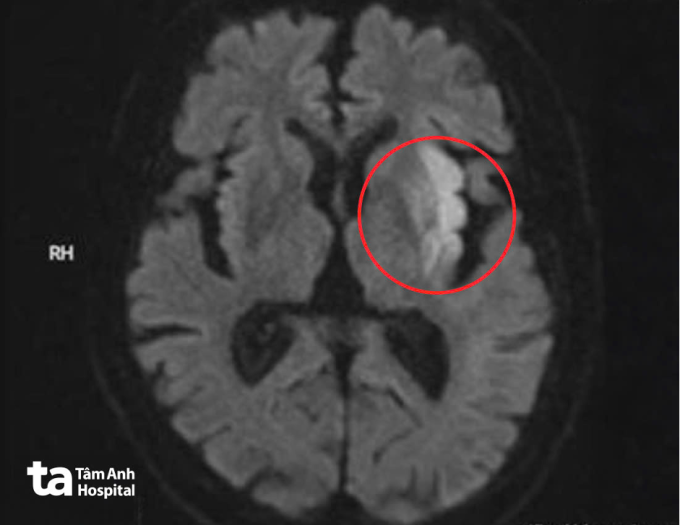

Bệnh viện kích hoạt quy trình "Code Stroke" tạo lối riêng cấp cứu đột quỵ. Kết quả chụp MRI 3 Tesla não của ông Trung cho thấy ổ nhồi máu cấp tại vùng nhân bèo, thùy trán và thùy đảo trái, kèm hình ảnh mất tín hiệu đoạn M1 động mạch não giữa trái, xác định tắc nghẽn mạch hoàn toàn.